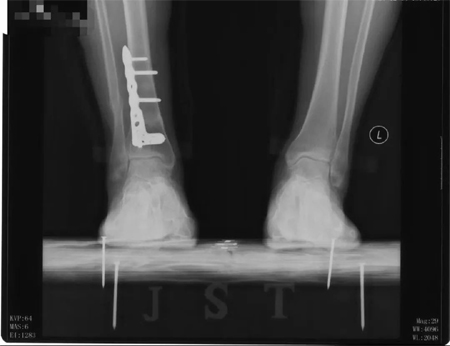

本次手术前,患者双侧踝关节的x片,可见右侧踝关节截骨术后改变,矫正角度良好,左侧为早期轻度内翻型踝关节炎。

术后第二天,患者踝关节的X片,可见截骨矫形满意,内固定位置满意可靠。